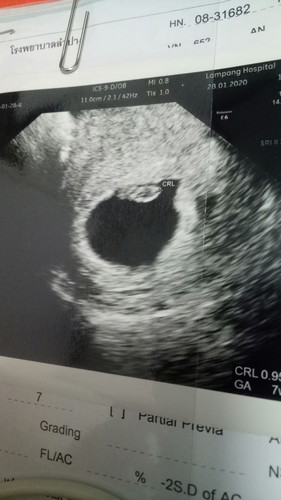

คบกับแฟนมาเปนปีมีทะเลาะกันบ้างตามประสาง้อกันดีกัน แต่ก้รักกันดี จนมาวันนึงบอกแฟนว่าท้องโอเคแฟนรับได้ แม่แฟนรับได้ แต่ชีวิตคู่คำว่าแฟนมันก้ไม่ได้ดีราบรื่นเสมอไป เราท้องได้7วีคแฟนหรือสามีเริ่มไม่สนใจเรา เราพยายามนะ พยายามทน พยายามเดินเข้าหา แต่กลับเปนสามีเราที่เฉยแร้วเดินออกห่าง จนมาวันนี้ตอนนี้ เราตัดสินใจบอกสามีไปว่าต่างคนต่างอยู่ พี่ไม่มีสิทธิ์ในตัวนู๋กับลูกอีกต่อไปในเมื่อพี่เลือกที่จะทิ้งพวกเรา ถามว่าเสียใจมั้ย เสียใจนะ แต่ก้ต้องสู้ เพื่อ...ลูก #คุณแม่เลี้ยงเดี่ยว ไม่ว่ายังไงแม่คนนี้ก้จะไม่ทิ้งลูกเหมือนที่พ่อเค้าทิ้งเรา รักลูกนะ